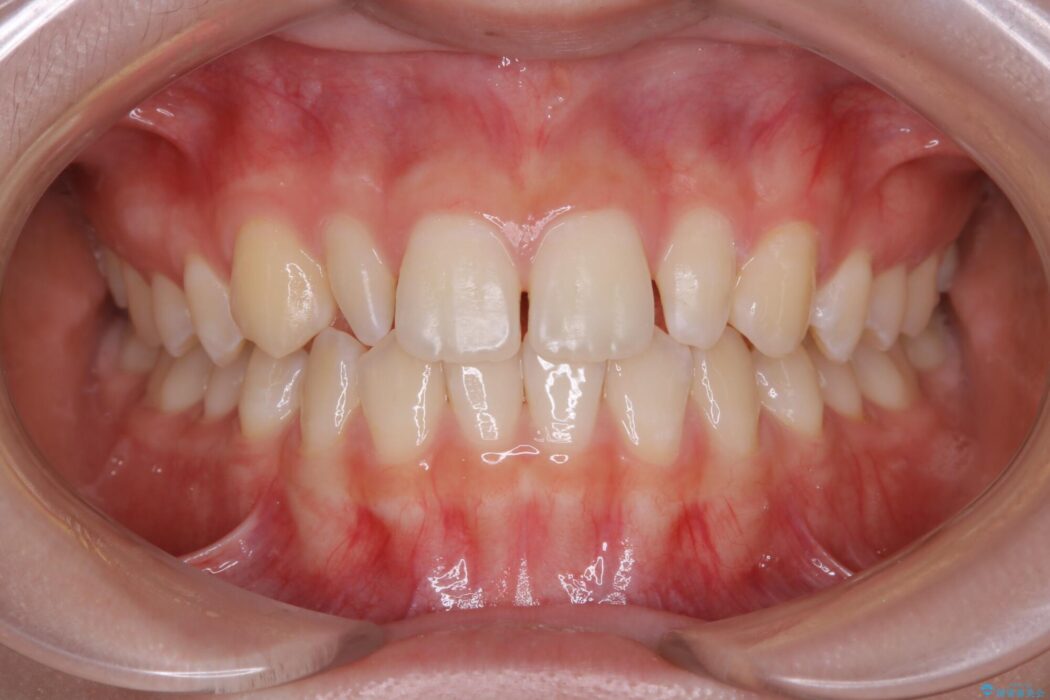

【50代女性】八重歯のインビザライン矯正 治療例

八重歯の改善を希望され来院されました。

頻繁にご来院いただく事が難しかったこともあり、型取りのし直し(リファインメント)を2回行いました。時間はかかってしまいましたが、患者様には大変ご満足していただくことができました。